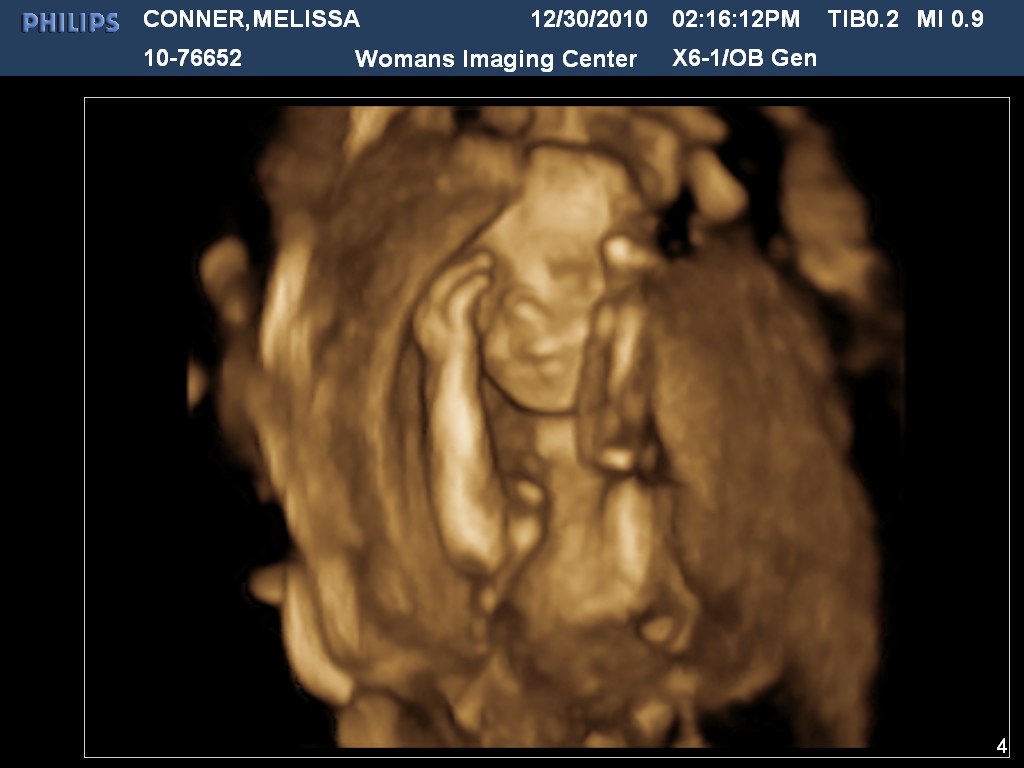

Yesterday, Jarrod, Elliot, and I had our 20 week dr. appointment. It started off with the ultra-sound tech, where she took measurements, counted bones, fingers, and toes. Jarrod didn't get to go in there with me at first so I tried to close my eyes so we could experience everything together. Yeah, FAT CHANCE! It was so cool to watch her just hang out inside me!

After we had the ultra-sound, we had an actual dr. appointment with my OB. She looked over my paperwork and said everything looks great. She was VERY impressed with my blood work results. We decided to have the downs test done and the results came back that Elliot has a 1/12000 chance of having it. Other than mine, the lowest percentage she had seen was 1/300. We'll attribute that to awesome Edwards genes ;). She gave me "Tylenol Plus" for my headaches, told me to get lots of rest, and sent us on our merry way!